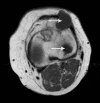

Case presentation: In this report, we describe the case of a 49-year-old Caucasian woman known for years to have fibrous dysplasia in the left femur and tibia who presented with progressive pain in her left leg and soft swelling in the left quadriceps region. After surgical intervention with excision of the soft-tissue mass, the diagnosis of Mazabraud's syndrome was confirmed. During follow-up, our patient presented with a painless mass located on the lateral side of the left knee, next to a second, intra-osseous lesion with the same characteristics in the left lateral tibial plateau. The histopathological examination was consistent with a soft-tissue intra-osseous myxoma.